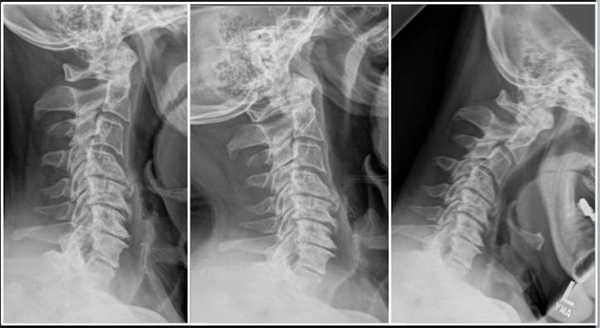

Подготовка к операции на шейном отделе позвоночника

Сначала врач направляет пациента на комплексное клиническое обследование, результаты которого становятся более понятны после визуализационной диагностики. Клиническое обследование — это беседа с пациентом и физический осмотр. Визуализационное обследование — это рентген в положении "лежа" и "стоя", то есть под нагрузкой. Еще одним немаловажным моментов диагностики является МРТ (магнитно-резонансная томография). Таким образом определяется состояние межпозвоночных дисков и нервов в области позвоночника. Помимо этого, проводится измерение плотности костей для установления их стабильности, а также исключения остеопорозных изменений.